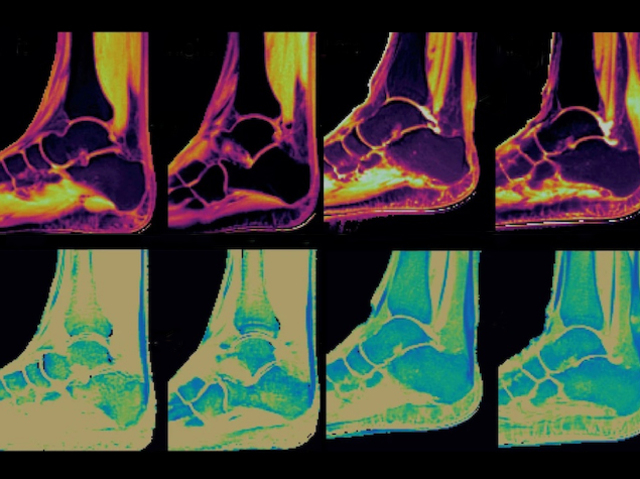

Looking Swell

Water and ions binding to the extracellular matrix (the network of supporting molecules around cells) in swollen tissue exploited to enhance MRI scan detection of the injury